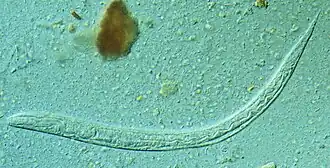

![]() Личинка Strongyloides stercoralis | |

Стронгилоидо́з (лат. strongyloidosis, ангвиллюлёз, кохинхинская диарея) — паразитарное заболевание человека, вызываемое круглыми червями рода Strongyloides, преимущественно Strongyloides stercoralis. Характерной особенностью данных паразитов является способность с одной стороны жить и размножаться в организме хозяина десятилетиями практически бессимптомно, а с другой — вызывать угрожающие жизни состояния у людей со сниженным иммунитетом (диссеминированный стронгилоидоз со смертностью 60—85 %)[3].